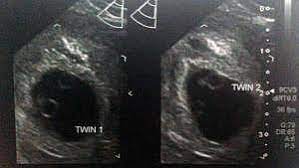

We had the wonderful opportunity to see our baby's heart flickering on the screen!!! They said the doctor will call me and they may book an ultrasound in another two weeks. By four weeks, twins will start showing during ultrasound in form of 2 gestational sacs, but you cannot get clear indication of twins until 6 weeks. The ultrasound image is of twins at 4 weeks. No fetal heartbeat detectable at 5 weeks 6 days ultrasound.

Between 5 ½ to 6 ½ weeks, a fetal pole or even a fetal heartbeat may be detected by vaginal ultrasound. In this 7th week of pregnancy, your baby's lungs are starting to develop. The ultrasound picture above is of identical twins who share a placenta at 6+2 weeks. Beauty points sammeln & mit der douglas beauty card von exklusiven vorteilen profitieren. This begins with a small lung bud branching out from the upper part of the tube (esophagus) between your baby's mouth. Get to know what you need to take care of when 4 weeks and 6 days pregnant pregnant. I've been posting in october 2012 since i found out i was pregnant in february. You have approximately a 3.35 chance of having twins naturally , without the help of any fertility treatments. They said the baby looked small and measured about 6 weeks. 4 weeks) between 5 ½ to 6 ½ weeks, a fetal pole or even a fetal heartbeat may be detected by vaginal ultrasound. Little arms and legs sprout. You don't hear heartbeats any earlier or later with twins, that i know of. Mehr als 200.000 maschinen sofort verfügbar.